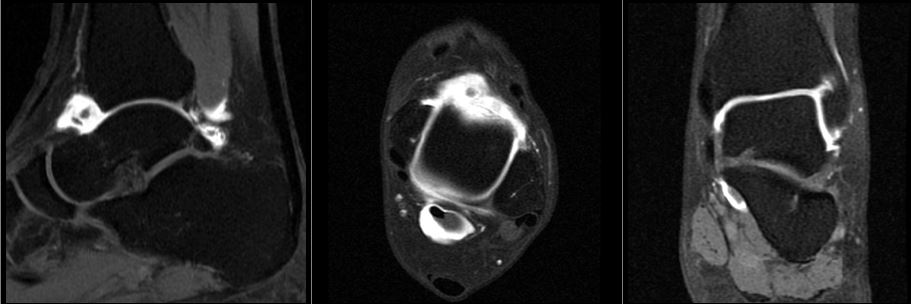

Mri Arthrogram Hip Protocol And Planning Indications For Mri Arthrogram Hip Scan